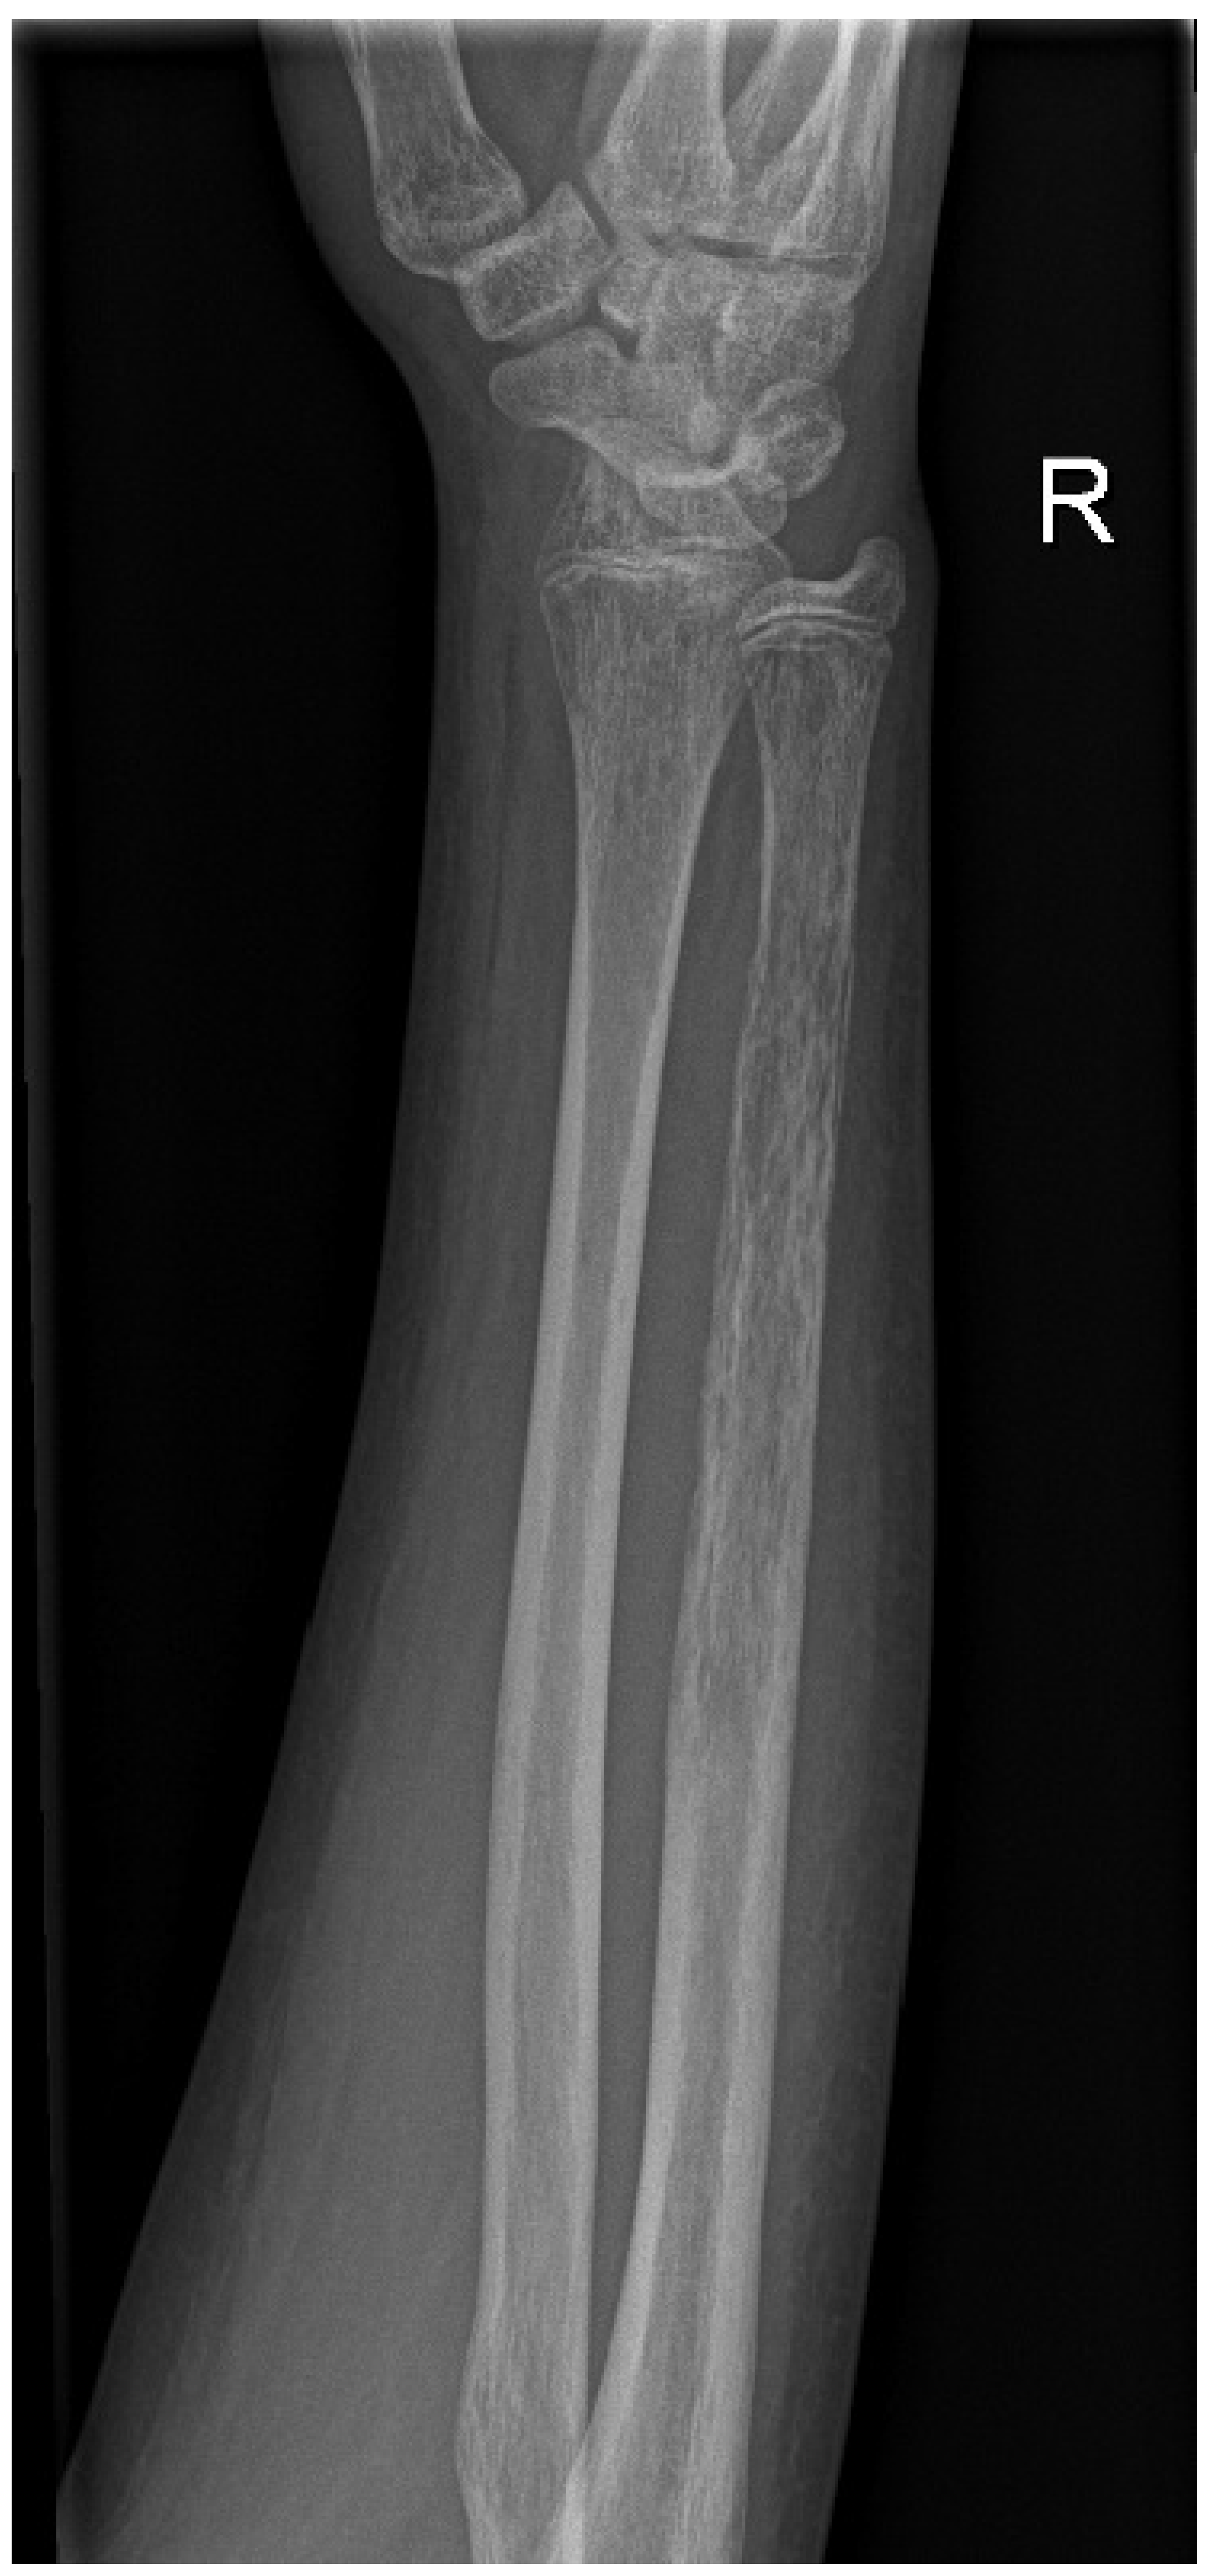

In view of the patient’s high-risk leukaemia, the following treatment was decided for conditioning: total body irradiation (TBI) with 12 gray total doses (delivered in four fractions on pre-transplant days 8–4), combined with etoposide-phosphate (60 mg/kg on pre-transplant day 2) and anti-thymocyte globulin (15 mg/kg between pre-transplant days 4–1) [19]. At the start of the conditioning, white blood cell and neutrophil cell counts were in the normal range. His anti-infectious prophylactic regimen included levofloxacin, acyclovir, and posaconazole. Shortly before the planned TBI, the patient had become febrile and empiric piperacillin/tazobactam had been initiated. Considering the patient’s overall stable state, with no markedly increased inflammatory parameters, the decision was made for commencing the irradiation therapy. The patient remained afebrile during the first days of the irradiation. Later, however, a marked surge of CRP and procalcitonin was observed. Moreover, significant pain and swelling of the right forearm developed. As the procalcitonin surge correlated with the irradiation, the possibility of malignancy was not dismissed. Radiography of the right forearm proposed extensive osteomyelitis based on the thinned cortex, a pattern of cortical destruction and a periosteal reaction (Figure 1). Upon getting new clues for a presumed infection and consultation with orthopaedic surgeons, the patient’s anti-microbial treatment was changed to meropenem—vancomycin combination, and he was immediately admitted to an orthopaedic/trauma unit after the completion of the TBI. Surgical irrigation and thorough debridement were performed on the right ulna, which presented the picture of extensive, purulent-necrotic osteomyelitis. Gentamicin-containing polymethyl methacrylate beads were placed into the evacuated marrow. The radius of the same forearm remained unaffected.

Figure 1.

Radiography of the right forearm: thinned cortex, a pattern of cortical destruction and periosteal reaction of the ulna.